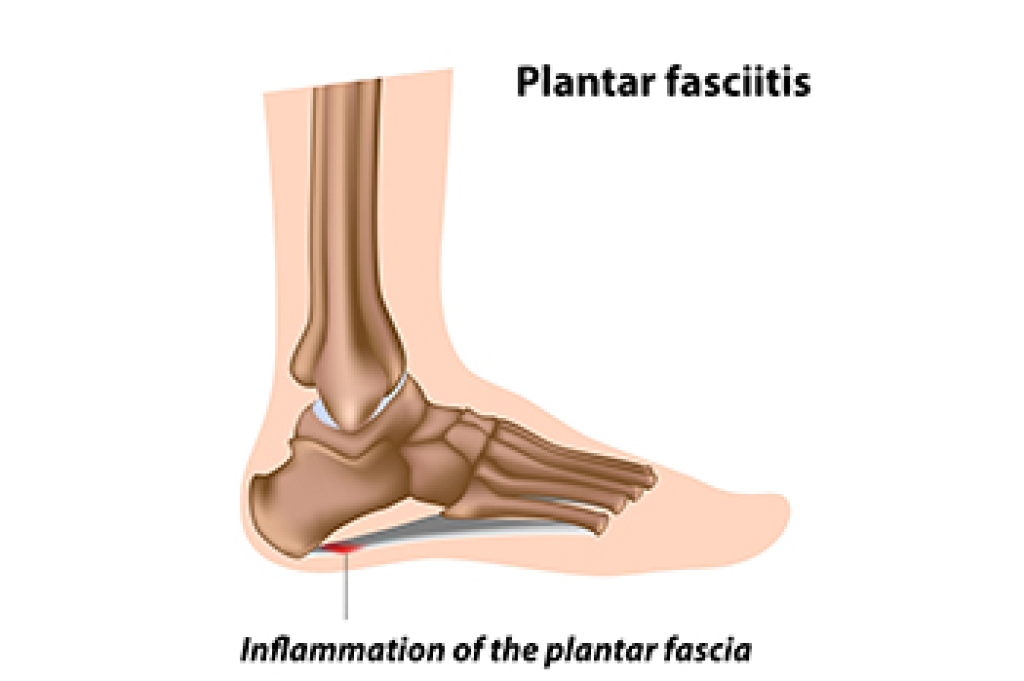

- Plantar fasciitis is also another common injury.